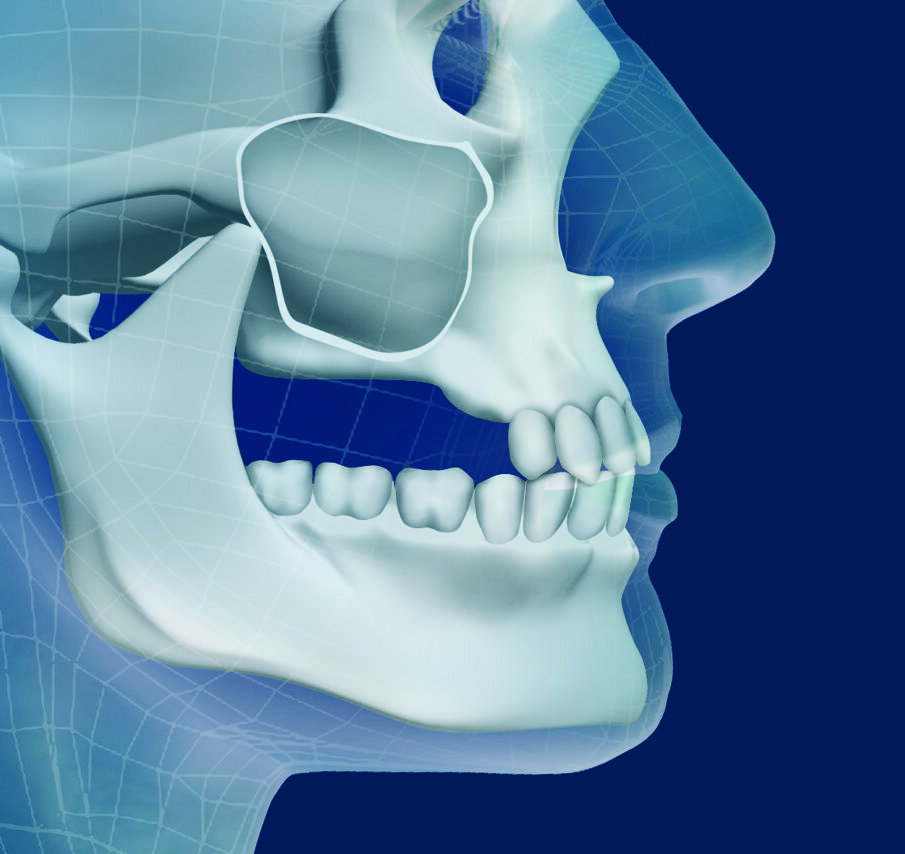

Un paziente candidato a elevazione del seno mascellare, che ha perso tutti gli elementi latero-posteriori, si presenta solitamente con un riassorbimento osseo sia di tipo verticale che orizzontale (Figg. 1, 2); è dunque fondamentale valutare con attenzione questo quadro clinico prima di sottoporre il soggetto all’intervento. Una mancata analisi di queste informazioni indurrebbe una gestione della fase chirurgica priva della corretta valutazione della fase protesica, esitando quindi in restauri protesici incongrui e difficilmente mantenibili da un punto di vista igienico nel medio-lungo termine. Da letteratura tradizionale l’indicazione per l’elevazione del seno è l’atrofia moderata del mascellare superiore con moderato riassorbimento osseo verticale ed orizzontale6. Questo consente di realizzare elementi protesici con lunghezza apico-coronale aumentata di non più del 20% (solitamente 1,5-2 mm) rispetto agli elementi naturali controlaterali.

Figg. 1, 2_Schema di atrofia ossea verticale e trasversale posteriore del mascellare superiore.